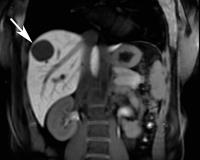

Echinokokkus - Leber

Abbildung 2

Echinococcus granulosus

,

Hepatologie

Leber

Magnetresonanztomographie